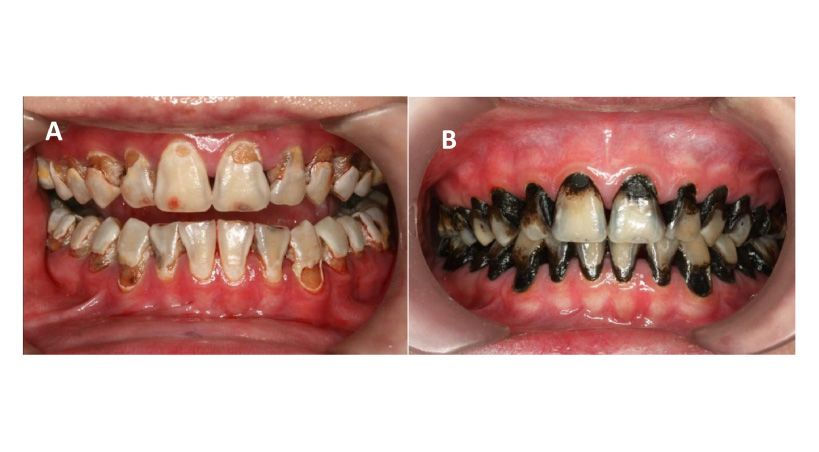

1. Mancha negra permanente

El mayor problema estético del nitrato de plata es que tiñe de negro el tejido dental cariado, dejando una apariencia poco agradable, especialmente en dientes frontales. Esta pigmentación es permanente y no puede eliminarse con limpieza.